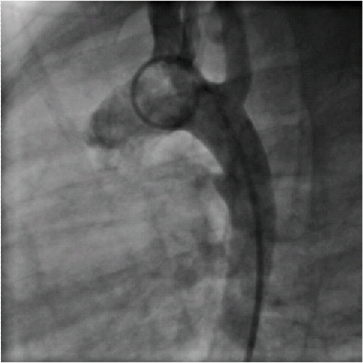

PDA anne karnında açık olan ve dolaşımı sağlayan kanalın, doğumdan sonra kapanmayıp açık olarak devam etmesidir. Bu açıklığın boyutuna göre hastanın yakınmaları değişir. Bazen hiçbir yakınma yapmayıp tesadüfen saptanır, bazen de ağır kalp yetersizliğine ve ciddi sorunlara yal açabilir. Bugün PDA larda güncel tedavi genellikle amaliyatsız (girişimsel yöntemler) kapatma şeklindedir…Alttaki resimde PDA açıklığı ve coil ile başarı ile kapatılmış PDA yı görmektesiniz…Bu hasta için çok konforlu bi işlemdir ve hastayı ameliyattan kurtarır…